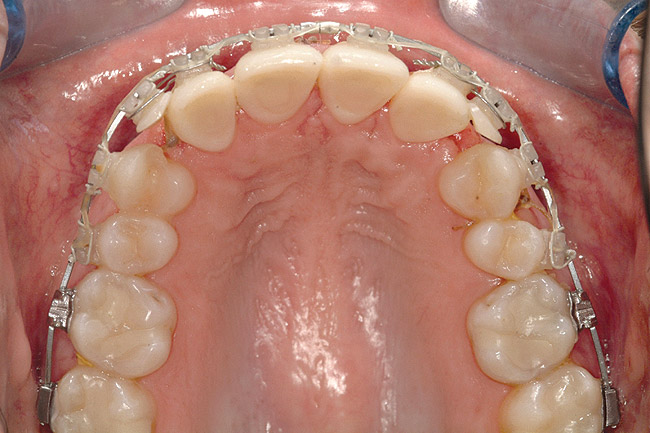

Fig 18 (through Fig 21). Note lack of alveolar development from congenitally missing Nos. 24 and 25. Surgical procedures after 5 months of orthodontic alignment included single-tooth osteotomies Nos. 6 to 11 and Nos. 21 to 28 and buccal corticotomies on all other teeth. Anchorage plate was stabilized to piriform rim.

Fig 20. Note lack of alveolar development from congenitally missing Nos. 24 and 25. Surgical procedures after 5 months of orthodontic alignment included single-tooth osteotomies Nos. 6 to 11 and Nos. 21 to 28 and buccal corticotomies on all other teeth. Anchorage plate was stabilized to piriform rim.

Fig 21 (and Fig 20). There is significant lateral dentoalveolar expansion of arches and alveoloskeletal correction in maxillary and mandibular anterior regions. Alveolar bone volume was increased in lower anterior to create optimal implant sites and establish ideal interincisal function and stability.